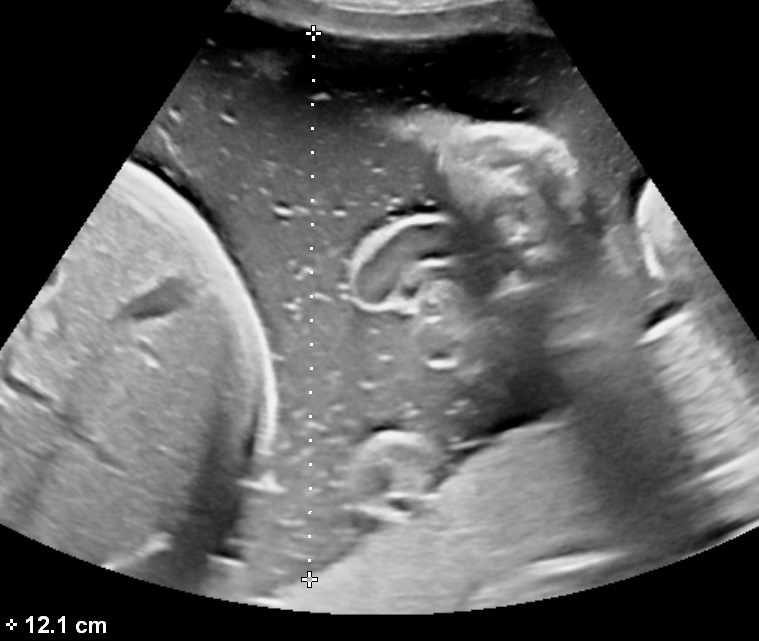

Measure the Fetal Head

fetal head biometry